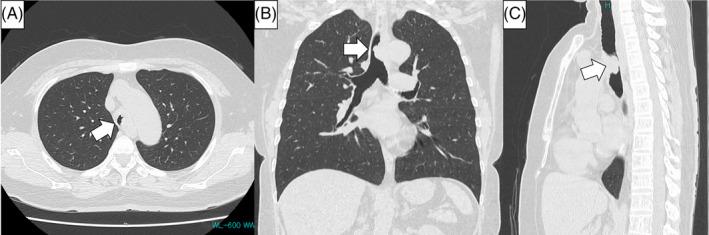

There is no standard method of bronchoscopic local therapy for tracheal tumours. We herein present a case involving a 61-year-old woman who was diagnosed with tracheal mucosa-associated lymphoid tissue lymphoma and underwent resection by a bronchoscopic high-frequency electrosurgical snare. Few reports to date have described such use of high-frequency electrosurgical snares; however, they are effective for the treatment of tracheal tumours, especially pedunculated tumours.

目前尚无针对气管肿瘤的标准支气管镜局部治疗方法。我们在此报告一例61岁女性患者,该患者被诊断为气管黏膜相关淋巴组织淋巴瘤,并接受了支气管镜高频电圈套切除术。迄今为止,很少有报告描述高频电圈套器的这种应用;然而,它们对气管肿瘤,尤其是带蒂肿瘤的治疗是有效的。